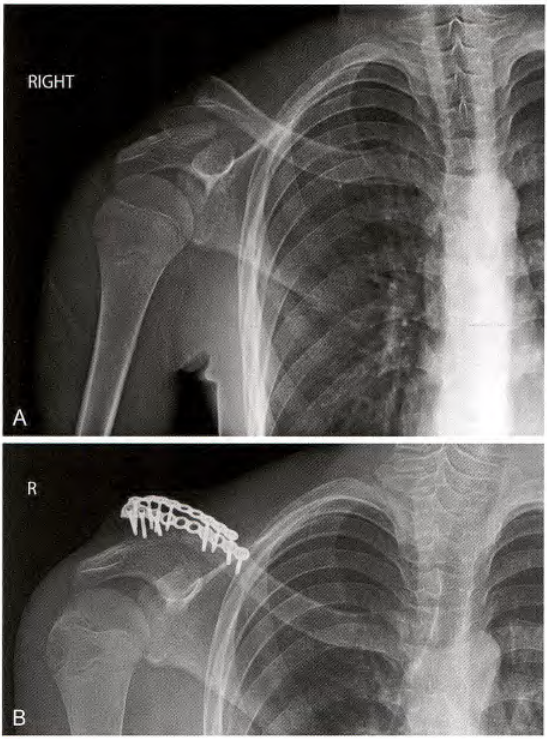

钢板和螺钉固定

A.锁骨骨折, B.前方钢板固定